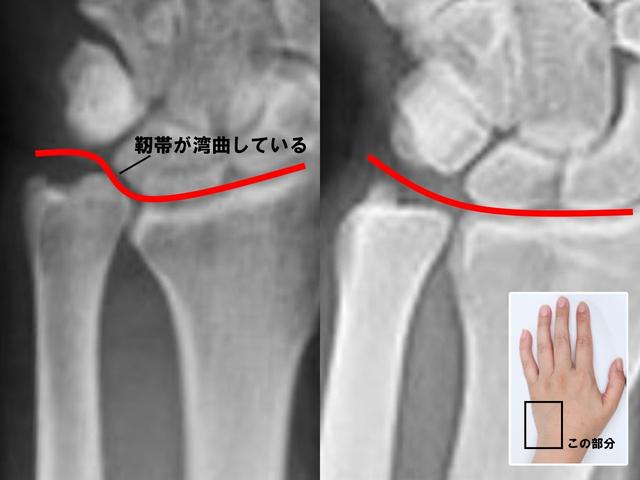

左手首のレントゲンの比較

TFCC損傷の左手首(画像左)、正常な左手首(画像右)

具体的に、手首の小指側にある軟骨と靭帯の3つの複合体で、小指側にある尺骨と呼ばれる突起した骨の脇のくぼみ辺りにあります。ゴルフやテニスなどの手を使うスポーツ、重たいものを運んだりする重労働や私生活などで、手首を繰り返し酷使した場合に小指側にある尺骨が突き上がってしまうことがあり、その際に小指側の複合体から手首を横切る靭帯の一つが突き上がった尺骨の上をゆがみながら横切ることになり、靭帯が緩んでしまう状態を『TFCC損傷』といいます」